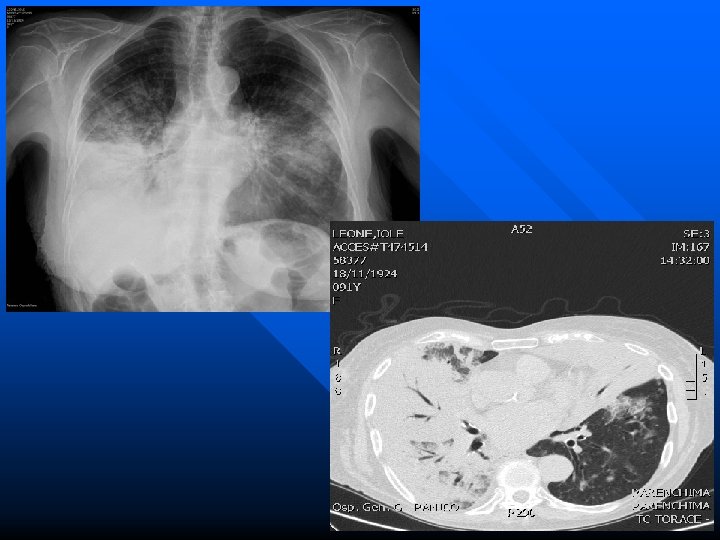

RX: Ascesso lobo sup. dx Immagine TAC

Ascesso polmonare Dopo terapia

Rx torace base Rx Torace dopo terapia